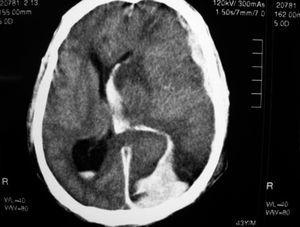

Presentamos un varón de 43 años, con infección por el virus de la inmunodeficiencia humana (VIH), sin seguimiento ni tratamiento antirretroviral, adicto a drogas por vía parenteral, que acudió a urgencias por 7 días de astenia, fiebre y disnea progresiva. Presentaba múltiples signos de venopunción y, aunque afebril, estaba afectado, sudoroso, taquicárdico y taquipneico, con crepitantes gruesos bibasales en la auscultación. La exploración neurológica inicial fue normal. En la analítica destacaba leucocitosis con neutrofilia, 37.000 plaquetas, actividad de protrombina del 55%, índice normalizado internacional (INR) de 1,6, y elevación de creatinfosfocinasa, transaminasas y bilirrubina. El electrocardiograma mostró taquicardia sinusal. La gasometría arterial inicial mostraba hipoxemia, con posterior evolución a insuficiencia respiratoria global y acidosis, iniciándose tratamiento con broncodilatadores y corticoides. En Urgencias el paciente sufrió deterioro brusco del nivel de conciencia con anisocoria, y fue preciso canalizar vía central y proceder a intubación orotraqueal. Se realizó tomografía computarizada (TC) craneal sin contraste (fig. 1), que mostraba hematoma subdural agudo frontoparietal izquierdo, hemorragia subaracnoidea en hemisferio cerebral izquierdo y tentorio, hematoma en lóbulo occipital izquierdo con edema periférico y herniación transtentorial y subfalcina. Tras extracción de hemocultivos se inició tratamiento parenteral con cefotaxima (2 g) y clindamicina (600 mg) para cubrir posible aspiración.

Figura 1. TC craneal inicial (sin contraste): hematoma subdural agudo frontoparietal izquierdo; hemorragia subaracnoidea en hemisferio cerebral izquierdo y en tentorio; hematoma en lóbulo occipital izquierdo, con edema periférico; y herniación transtentorial y subfalcina.